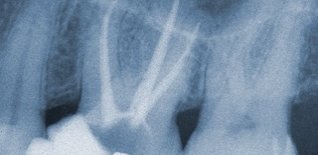

Detersione, sagomatura

e chiusura tridimensionale del canale.

È quella branca dellʼodontoiatria che studia le comunemente dette devitalizzazioni: questo è il punto di partenza principale della maggior parte dei piani di trattamento protesici sui denti naturali ed è quindi estremamente importante una corretta esecuzione nei tempi e nelle tecniche per la durata a lungo termine del trattamento protesico finale.

Anche in questo settore la tecnologia dà una mano con nuove strumentazioni, quali i rivelatori apicali e le strumentazioni meccaniche (non più solo manuali) per ottenere i tre punti fondamentali per il successo: detersione, sagomatura e chiusura tridimensionale del canale.